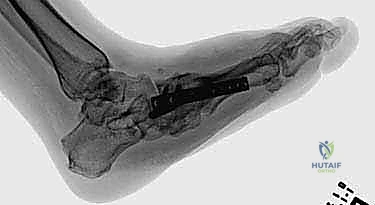

الخطوة الرابعة: إعادة بناء وتثبيت المفاصل (Arthrodesis)

هذه هي المرحلة الأهم، حيث يتم دمج العظام المتضررة معاً لتكوين كتلة عظمية صلبة ومستقرة. يعتمد الدكتور هطيف على تقنيتين رئيسيتين حسب حالة المريض:

ب) التثبيت الخارجي الحلقي (جهاز إليزروف - Ilizarov Apparatus):

يُعد الأستاذ الدكتور محمد هطيف من أبرز الخبراء في استخدام جهاز إليزروف في اليمن. يُستخدم هذا الجهاز عندما تكون جودة العظام سيئة جداً أو في حالة وجود التهاب أو قرحة مفتوحة تمنع وضع معادن داخلية. عبارة عن حلقات معدنية تحيط بالقدم والساق، متصلة بأسلاك دقيقة تخترق العظام، مما يوفر ثباتاً ميكانيكياً هائلاً ويسمح للمريض بالمشي التدريجي أثناء فترة الالتئام.